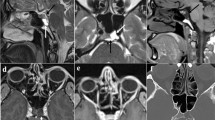

An 18-month-old boy (patient 1) with a nasal dermal sinus cyst (NDSC). A Axial CT shows a midline soft tissue mass (arrow) with widening of the foramen caecum and the nasal septum. B Axial T2-rapid acquisition with relaxation enhancement (RARE) confirms an isointense soft tissue mass within the anterior nasal septum next to the foramen caecum (arrow). C Sagittal T1-weighted spin-echo (SE) images show the isointense soft tissue mass (lower arrow) near the anterior skull base with a questionable neighbouring intracranial, extradural component (upper arrow). D Coronal T2-weighted RARE confirms the anterior skull base defect or widened foramen caecum (arrows) as well as the bifid, eroded crista galli. On surgical exploration the cranial extension of the lesion was negative for neuroectodermal components and was diagnosed as a fibrous stalk

Evaluating the individual indirect imaging signs (Table 2), CT and MRI were concordant in all patients. In 1 patient (patient 3) an erosion of a bifid crista galli that was displayed by CT was not seen on MRI. The bifid anatomy was, however, depicted equally good by both CT and MRI. By combining the indirect imaging signs, CT and MRI equally well predicted intracranial extension (10 of 11). In 1 patient (patient 1), both CT and MRI predicted intracranial extension which could not be confirmed at surgery.

Evaluating the direct imaging signs (Table 2), CT and MRI correlated with the surgical findings in 9 of 11 patients. The MRI showed, however, an intracranial, extradural signal alteration, indicating intracranial lesion location/extension, in 2 patients (patients 1 and 2) without a corresponding correlate on CT. In the first patient indirect imaging signs also indicated intracranial extension; in the second patient the indirect imaging signs did not support an intracranial lesion location/extension. In both patients the fistula was macroscopically followed by a fibrous stalk superiorly that was delivered and resected up to the foramen caecum. Microscopic analysis of the resected tissue confirmed the macroscopic findings. Because no direct intracranial extension was found, no intracranial surgical exploration was performed. Additional imaging findings included an eroded nasal bone in 3 patients (patients 1, 3 and 4), and a widened nasal septum in 2 patients (patients 1 and 3).

Our results showed that the direct imaging signs for intracranial extension in CT matched the final surgical/histological findings in all patients. Considering the direct imaging signs, MRI appeared false positive in 2 children with NDSC. A subtle intracranial, extradural signal alteration was encountered on MRI that was not confirmed on surgical exploration (Fig. 1). This does not, however, necessarily indicate that CT is more accurate than MRI in excluding intracranial lesion components. Especially as in one of these 2 patients, the indirect CT and MRI imaging signs also suspected intracranial extension. More likely, these subtle extradural MRI signal abnormalities remained undetected by CT due to its lower soft tissue contrast. We speculate that intra- and extracranial lesion components can be simultaneously present despite an intact or unremarkable bony frontobasis. Two considerations are mentioned to underline this postulation. First of all, as stated previously, these lesions represent a spectrum of malformations along a common pathway of interaction and separation of the different germinal cell layers. Taking this into account, malformations with connected intra- and extracranial components and cases with solitary, either intracranial or extracranial, located lesions are theoretically expected to represent the extremes of this spectrum. Consequently, presentations should also be expected combining features of both extremes, which is the simultaneous appearance of an intracranial and extracranial component without a direct connection through the skull base. Secondly, the reliability of the so-called gold standard has to be reviewed in light of our first consideration. An intracranial extension is usually believed to be excluded if the cephalic end of the surgically removed extracranial nasal specimen or fibrous stalk is tested negative for ectodermal or neurogenic elements on multiple histological sections [24, 25]. Obviously, these results cannot exclude non-connected coexisting intracranial components; therefore, the consequences of these considerations are that the false-positive MRI findings in the first 2 patients with NDSC are maybe not false-positive findings but could represent definite pathology which got undetected by CT due to its lower soft tissue contrast resolution and by histology because this area was simply not explored. The clinical importance of these subtle extradural MRI findings are still to be studied, but it would mean that children should be followed-up after surgical removal of the extracranial mass to exclude a possible progression of intracranial MRI signal alterations.

In our experience, the high-resolution CT bone algorithm reconstruction facilitates the evaluation of the foramen caecum, the crista galli and cribriform plate compared with MRI. This limitation is, however, compensated by distinct advantages of MRI, which include direct sagittal imaging planes and the possibility to generate multiple tissue contrasts (e.g. T1- vs T2-weighted sequences). Direct sagittal planes can allow the visualisation of the entire lesion including the intracranial communication [10]. The different signal intensities can be used to differentiate the dignity of the lesion. For example, T1- and T2-hyperintense components within a lesion indicate fatty inclusions as in an NDSC (Fig. 2), whereas a lesion that is T1- and T2-isointense to the cerebral grey matter is most likely a nasal glioma (Fig. 4). For example, T1- and T2-hyperintense intralesional signals indicate fatty inclusions as in an NDSC (patient 4). A lesion with a T1- and T2-signal isointense to grey matter indicative of a nasal glioma (patient 6). Moreover, additional MR angiographic sequences can help to differentiate nasal gliomas from capillary haemangiomas. This differentiation can be difficult on clinical inspection as Hoeger et al. reported previously [21]. In addition, partial-volume effects with the adjacent dense ossified frontobasis can hide small extradural lesions in CT. Because the bony frontobasis is hypointense in MRI, small extradural, intracranial lesions near the skull are more easily identified on MRI. Finally, advances in MRI hard- and software allows to image the frontobasis with a progressive spatial resolution that allows to examine the foramen caecum, crista galli and cribrifom plate in a detail similar to high-resolution CT. In our study, the indirect CT and MRI imaging findings matched in all patients. No lesions were seen by CT that was not seen by MRI, and vice versa. The question concerning intracranial extension was based on the indirect imaging signs, answered similarly by CT and MRI. Consequently, our study could not support the hypothesis that CT is more advantagous than MRI in the evaluation of developmental nasal midline masses.